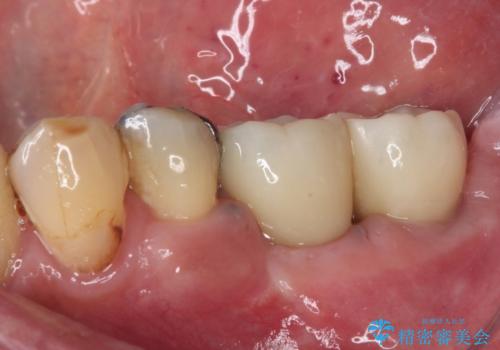

自分の歯のように噛めるようにしたいとのことで、インプラントによる欠損補綴治療を行うこととしました。

インプラントにはストローマン社のSLActiveを使用し、埋入から補綴までおよそ3か月と、短期間で治療を進めることができました。